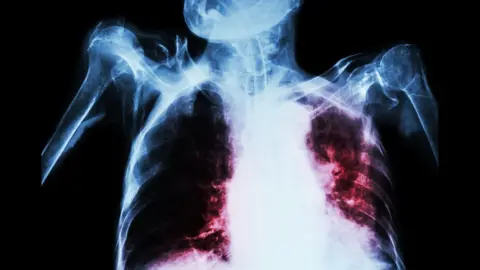

- TB is a bacterial infection spread through inhaling tiny droplets from the coughs or sneezes of an infected person

- It mainly affects the lungs, but it can affect any part of the body, including the tummy (abdomen) glands, bones and nervous system